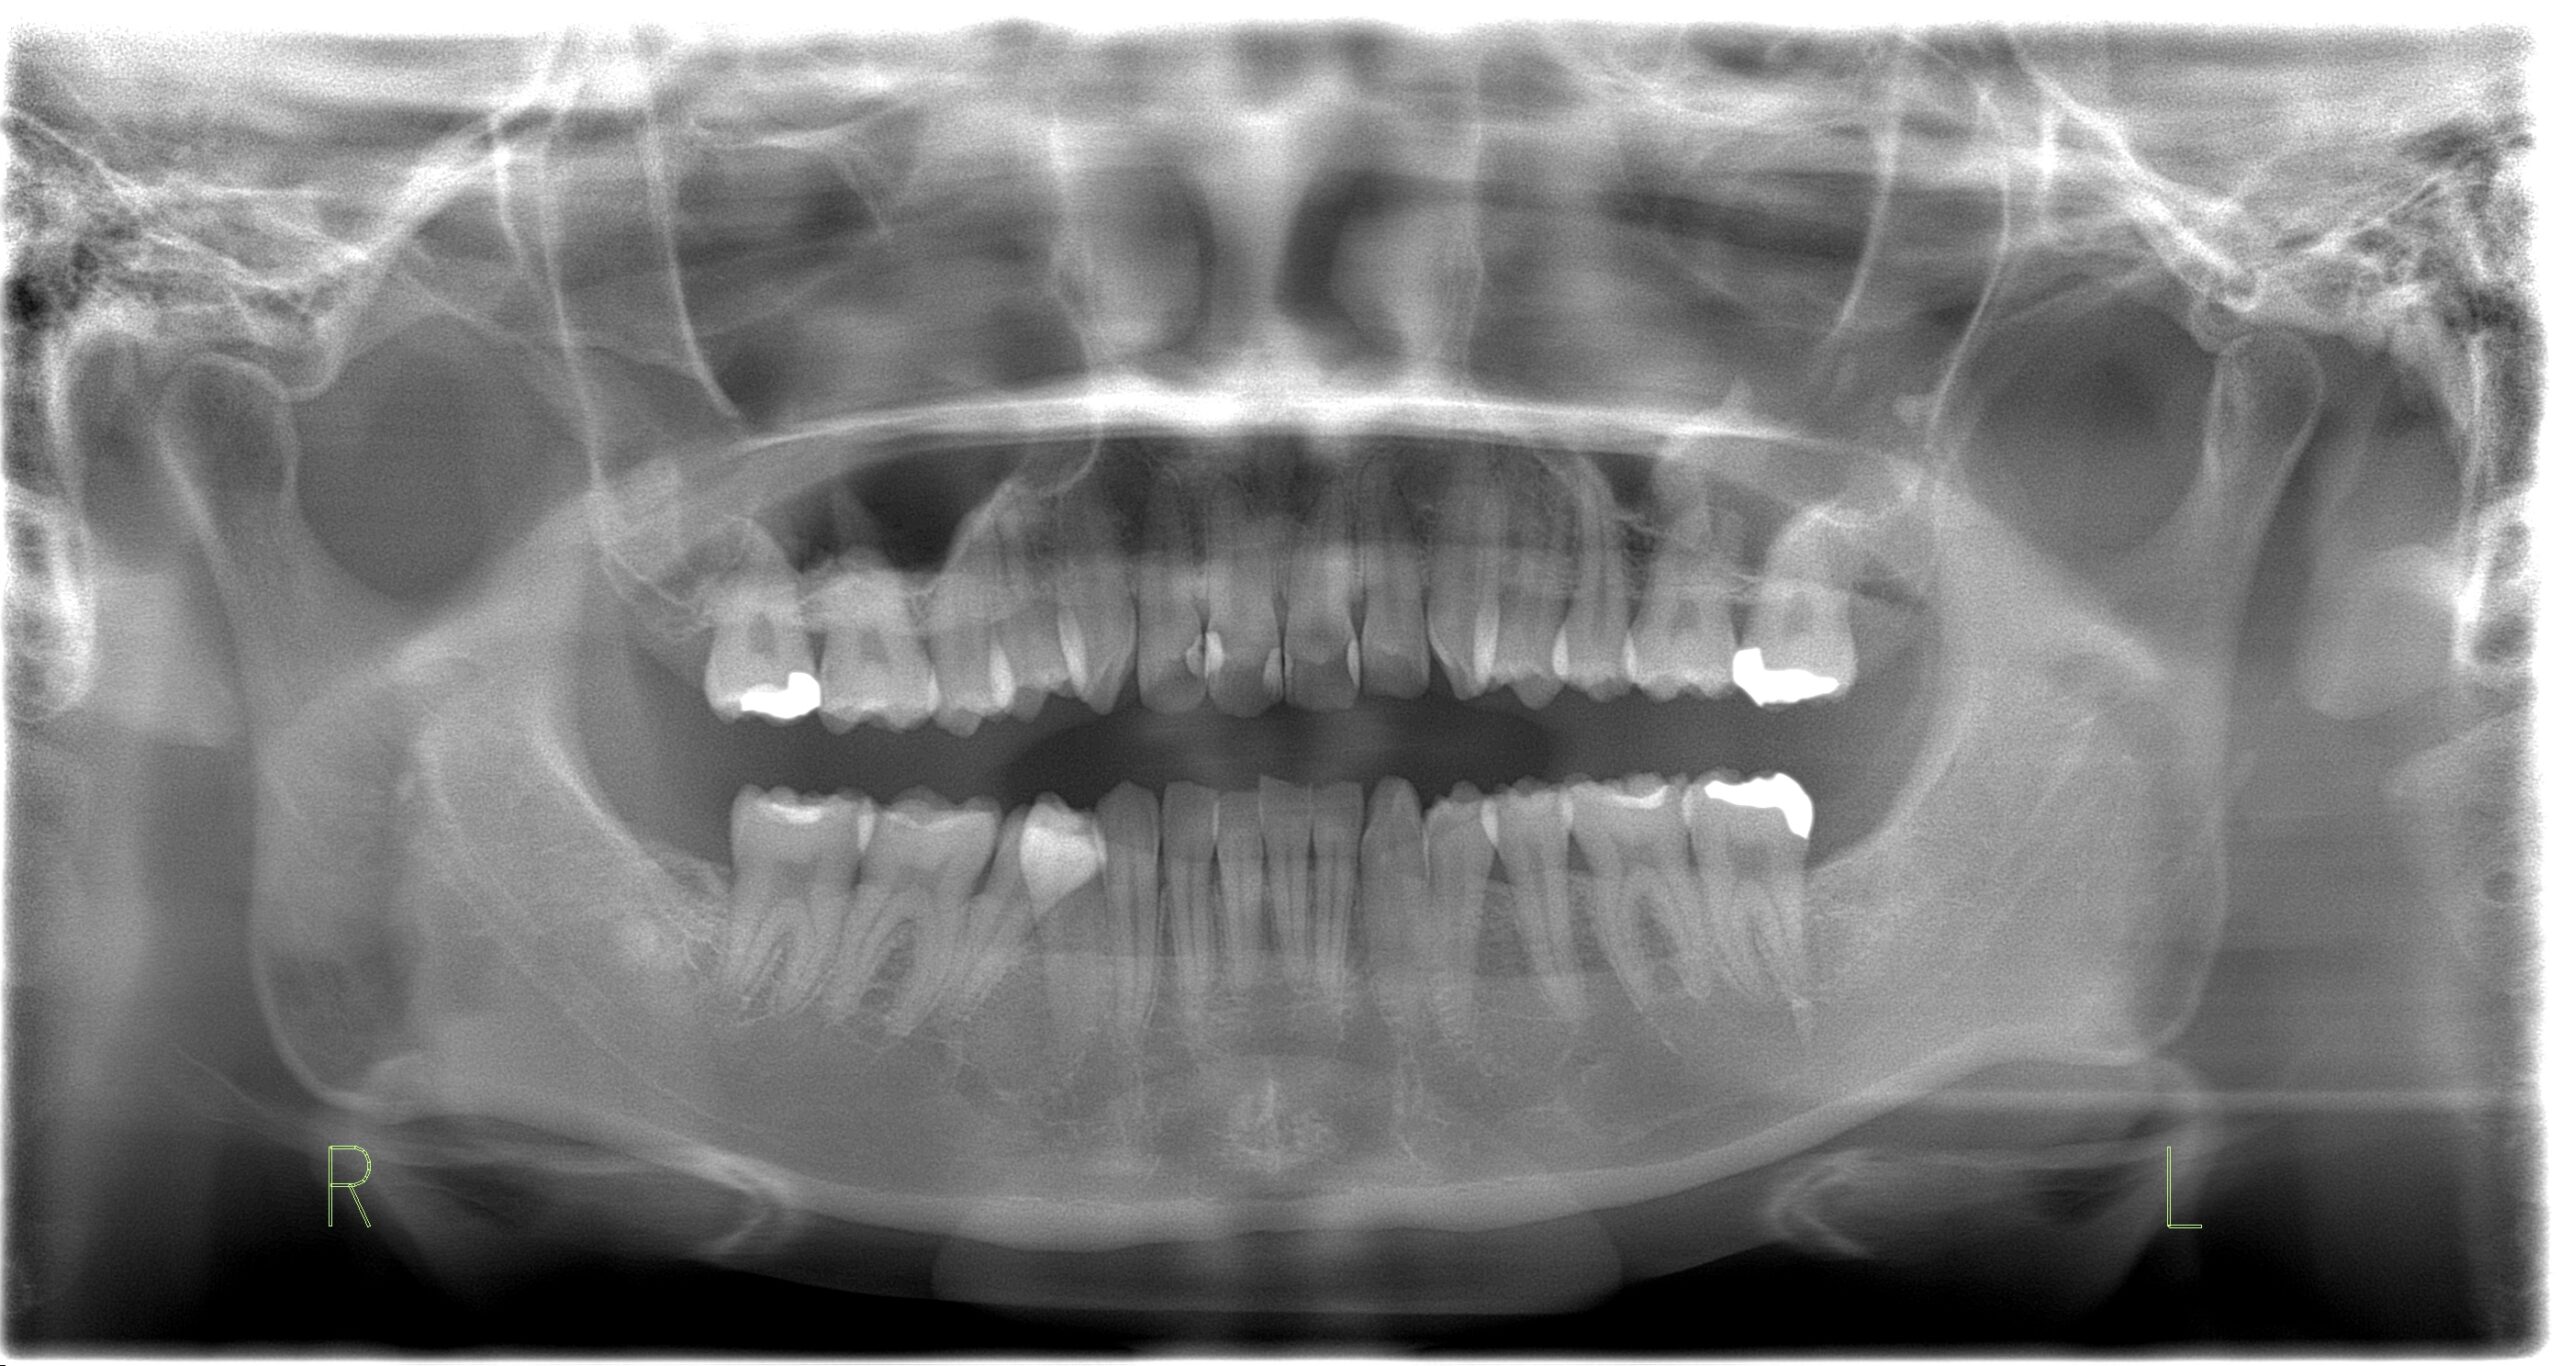

親知らずの抜歯 24歳女性

主訴 虫歯をなおしたい 診断名 親知らずの周囲炎 年齢・性別 24歳・女性 治療期間・回数 1ヶ月・2回 治療方法 左下の親知らずは下顎の骨の中の太い神経と近かったのでCT撮影をし、抜歯後のリスクは低いと判断して歯を抜きました。 費用 保険治療で約12,000円(2本抜歯) デメリット・注意点 数日間は痛みと腫れが出ます。

抜歯当日は激しい運動等、血のめぐりが良くなることはさけてください。

下顎の親知らず抜歯後は唇、舌にしびれが出ることがあります。 -